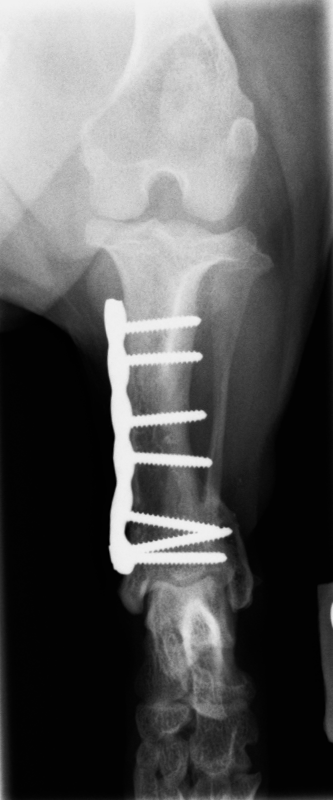

Diagnoosi voidaan varmistaa röntgenkuvauksella ja sairauden hoito on kirurginen. Sääriluun alapää katkaistaan ja luusta poistetaan kolmion muotoinen pala (kuva 2) niin, että jalka saadaan suoraan asentoon. Jalkaan asetetaan metallilevy (kuva 3A), joka poistetaan myöhemmin, kun leikkauskohta on täysin luutunut (kuva 3B). Fysioterapia leikkauksen jälkeen nopeuttaa paranemista. Ajoissa tehdyn leikkauksen ennuste on hyvä, ja suurin osa koirista elää leikkauksen jälkeen normaalin ontumattoman elämän.

Kuva 3: Heti leikkauksen jälkeen otettu röntgenkuva, jossa näkyy, kuinka jalan akseli on nyt suora (A) ja kolme kuukautta myöhemmin ennen levyn poistoa otettu röntgenkuva, jossa nähdään, että sääriluu on täysin luutunut ja jalka on oikeassa asennossa (B).